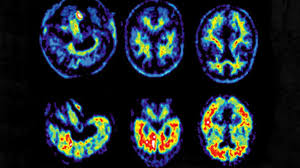

🧠 Alzheimer : un nouveau médicament prometteur

Des chercheurs en Angleterre ont développé un médicament, qui pourrait ralentir Alzheimer. Il agit sur la protéine Tau, responsable de la destruction des neurones.

Testé sur des mouches, il a réduit les dégâts dans le cerveau et prolongé leur vie. Des expériences sur des cellules humaines confirment qu’il fonctionne aussi sur nos neurones.

La prochaine étape : tester le médicament sur des souris, puis éventuellement chez l’homme. Cette avancée ouvre de nouvelles chances pour lutter contre Alzheimer.